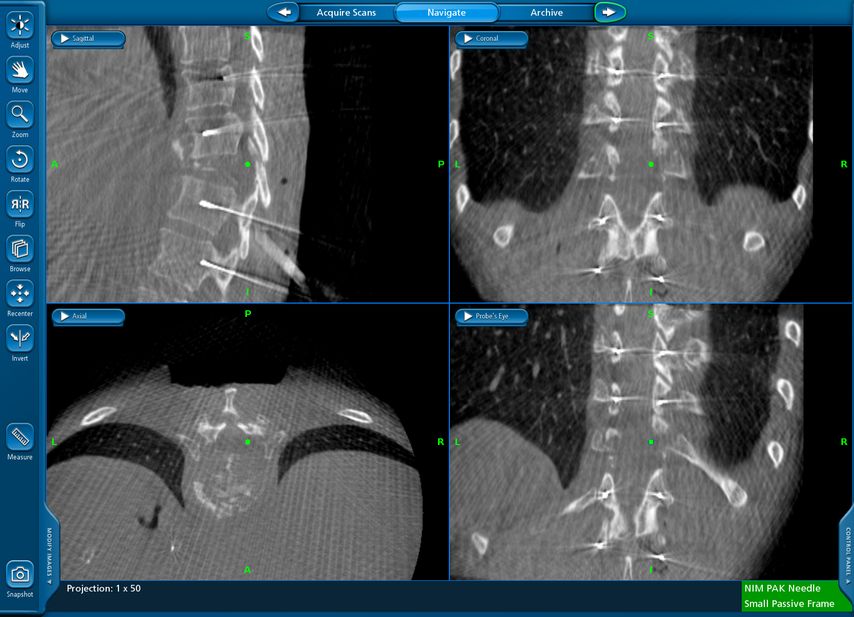

Beispiel für die Implantation zervikaler Pedikelschrauben. In diesem Fall kam es bei einem 61-jährigen Patienten 10 Jahre nach anteriorer zervikaler Diskektomie und Fusion (ACDF) C4/5 und ventraler Verplattung C4–6 zu einer Ankylosierung auch von C6/7. Nach Sturz kam es zu einer Fraktur bei C6/7 mit begleitender Bogenfraktur und auch Beteiligung der dorsalen Ligamenta (Abb. 1 und 2). Klinisch bestanden ausgeprägte Nackenschmerzen und kein neurologisches Defizit. Es wurde die Indikation der dorsalen Verschraubung von C4 auf Th1 gestellt. Intraoperativ wurde routinemäßig zusätzlich eine kleine Referenzschraube in einer Lamina – entfernt von der Dornfortsatz-Referenzklemme für die Navigation – gesetzt. Mit dieser konnte intraoperativ die Genauigkeit der Navigation exakt überprüft werden (Abb. 4 und 5). Mittels navigierter High-Speed-Fräse wurden die Schraubenkanäle vorgebohrt (Abb. 6), im Anschluss wurde der Bohrkanal ausgetastet und die Schrauben wurden implantiert. Abbildung 7 zeigt eine Röntgenkontrolle 3 Monate postoperativ.

Abb. 4: Screenshot der Navigationssoftware intraoperativ (Stealth Station S7). Es erfolgt die intraoperative Verifizierung der Navigationsgenauigkeit mittels kleiner Schraube in der Lamina, positioniert idealerweise entfernt von der Dornfortsatz-Referenzklemme. Die navigierte Fräse wird im Situs exakt auf die Schraubenmitte gerichtet, und die Navigation bestätigt die Genauigkeit | |